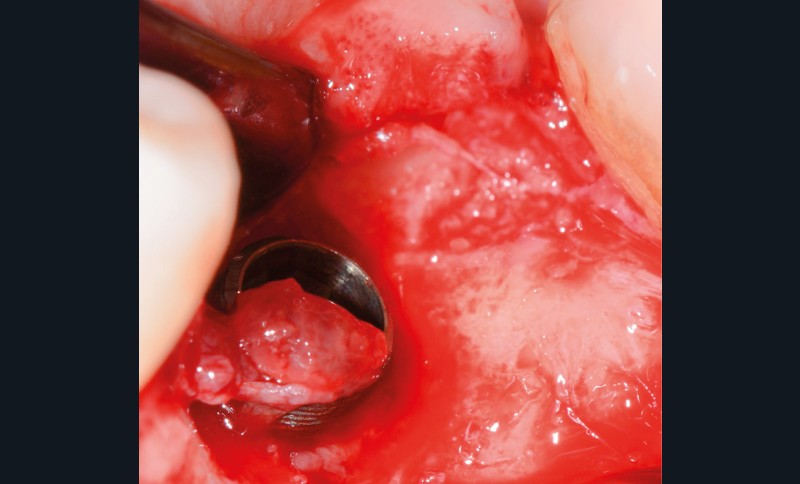

- Avulsion de la 36 et régénération osseuse guidée (ROG) réalisée en 2017 suite à une fracture de la dent et une infection

Chez ce patient, le traitement de la péri-implantite a comporté une chirurgie associant décontamination électrolytique de la surface implantaire, régénération osseuse guidée et enfouissement de l’implant. Le résultat à 2 ans est très moyen au vu du pourcentage de régénération osseuse obtenu. Comment peut-on prévoir un tel résultat alors que l’on a suivi les recommandations à la lettre, que l’on a utilisé les dernières technologies de décontamination, que l’on y a mis tous les moyens, que le patient est en bonne santé générale et qu’il vient en plus régulièrement aux séances de thérapeutique de soutien ? Le succès du traitement des péri-implantites n’est pas simple à obtenir, surtout quand un élément clé est compromis… la maintenance personnelle ! En effet le succès n’est possible que si le contrôle de plaque quotidien est optimal et, ici, ça n’était pas le cas. Le patient se brossait certes les dents, mais ne passait pas quotidiennement les brossettes, ce qui…